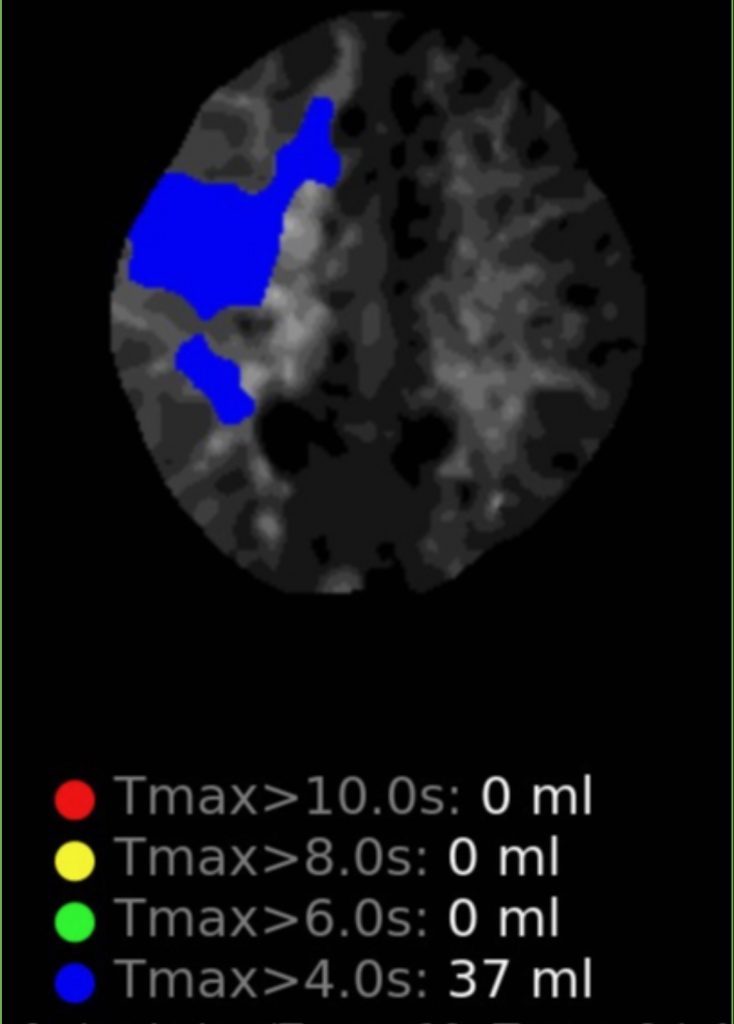

Noninvasive vascular imaging was sufficiently suggestive to warrant conventional digital subtraction angiography, performed by Dr. Brisman and confirming Moya-Moya syndrome (Figures 1). CT Perfusion (Figure 2) showed a decreased transit time of blood to the right hemisphere and the patient was recommended to undergo cerebral revascularization to avert stroke.